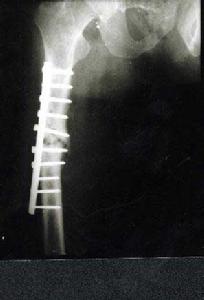

2、內固定法:近年來多主張用內固定療法,特別對年齡較高,不能耐受長期臥床的病人更為適用。。

2、閉合經距多根斯氏針內固定

先行脛骨結節牽引,進行復位,行全身系統檢查,傷後3~7d內在骨摺檯上手術。用4枚直徑3.5mm斯氏針同股骨頸骨折多根斯氏針固定術。

Gamma釘固定4、Ender釘固定

釘從股骨內髁上2cm處鑿孔,在X線電視螢光屏上觀察Ender針,穿過骨折部直達股骨頭關節面下0.5cm左右。使數根釘端呈扇形或魚叉樣散開,以固定近端骨塊。術後施皮牽引或防外鏇鞋。

5、Gamma釘固定

90年代初,一些國家採用Gamma釘,即一根帶鎖髓內針,斜穿一根通過股骨頭頸部粗螺絲釘,因主釘通過髓腔,從生物力學分析,力線離股骨頭中心近,因此,Gamma釘股骨內側可承受較大應力,可達到早期下地負重的目的。

PFNa是一種新型內固定系統,其特點在於頭釘為直徑螺鏇刀片,通過外側切口自動完成抗鏇轉鎖定,只打開外側皮質,不移除骨質即便是在骨質疏鬆非常嚴重的患者,仍可以感覺到螺鏇刀片牢固的錨合力,螺鏇刀片可以很順暢地鏇轉,當打入螺鏇刀片時不會發生股骨頭和股骨頸分離及股骨頭和股骨頸鏇轉,主釘具有6度外偏角,方便從大粗隆頂部插入;遠端一鎖定孔即可選擇靜態或動態鎖定;儘可能長的尖端及凹槽設計,使PFNA插入方便並且避免了局部應力集中;對於長型PFNA,也可以二期動態化。

PFNA特點有:屬於髓內固定,即保持了AO堅強固定的理念,生物力學穩定堅強,可早期下地行走。又體現了BO和微創外科的精髓,手術切口僅3~5cm,手術時間短,平均60min,出血少,平均72.2ml,不需輸血。頭釘為直徑11㎜的螺鏇刀片,導針只需一枚,且頭頸部位無需用鑽開孔,主釘6度外偏角,從大粗隆頂部即可插入,簡化了手術操作,縮短手術時間,降低了透視次數。PFNA具有多種型號,適應於Evans分型的各型轉子間骨折、對於轉子下骨折及合併股骨幹中上段骨折患者可選擇加長型。

綜上所述,套用PFNA治療股骨轉子間骨折具有固定確實,創傷小,下床活動早,骨折癒合快,併發症少等優點,是治療股骨粗隆間骨折的理想器械。